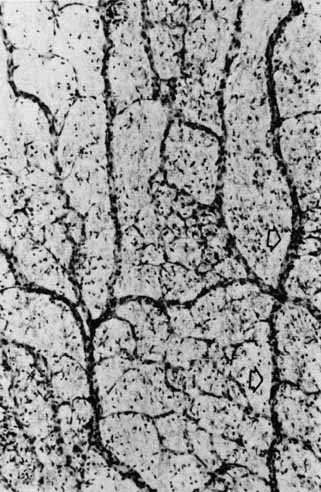

The photoreceptor outer segments have two important connections. One of these is to the inner segment, which is actually the cell body of the photoreceptor (see Fig. 21). The other connection is to the extracellular matrix that separates the photoreceptor outer segment from the pigment epithelial cell. Radioactive tracer experiments suggest that the sources of this extracellular matrix substance are the pigment epithelial and photoreceptor cells.99,100 The material, a glycoprotein consisting of chondroitin sulfate and sialic acid, is secreted into the space between the outer segments and the pigment epithelial cells by vesicles that originate in both cells. The function of this mucopolysaccharide-rich matrix is not well understood. It may provide a major route by which metabolites and nutrients pass between photoreceptor cells and their vascular supply. It may constitute the only intercellular bond between the outer segments of photoreceptors and the pigment epithelial cells, because there are no cellular connections such as tight junctions between these cells (see Fig. 23). Recent studies have identified interphotoreceptor retinol-binding protein as a major component of this matrix.100 This glycoprotein is believed to mediate the transport of a vitamin A derivative, retinol, between the photoreceptor and the pigment epithelium.

The connection of the outer to the inner segment of the photoreceptor is through a slender (0.2–0.3 μm in diameter) neck that is eccentric toward one side of the cell (see Fig. 21). The cilium, which is the embryonic basis for origin of the photoreceptors, is located in the neck and extends into the basal one third of the outer segment. It has nine pairs of microtubules. However, unlike motile cilia, the cilium has no microtubules centrally. The microtubules end in a modified centriole in the apex of the inner segment. The cilium functions as a conduit for metabolic materials going from the inner to the outer segments.

Inner Segments

The inner segment of the photoreceptor is the portion of the cell that metabolically services the outer segment. Whereas the outer segment shows high differentiation, containing only equipment necessary for the photoreceptor process, the inner segment possesses the cellular machinery essential for the metabolic and synthetic functions of the cell. There are two distinct morphologic regions in the inner segment, the ellipsoid and the myoid. The most prominent feature of the outer portion, or ellipsoid, of the inner segment is the abundance of large mitochondria at the apex (see Fig. 21). The ellipsoid appears to be more sensitive to anoxia than any other part of the photoreceptor cell.101 The staining characteristics of this area vary with the state of metabolic activity of the photoreceptor cell and may account for the subtle staining differences seen in the various types of photoreceptor cells. The mitochondria in the ellipsoid are compactly arranged. They are present in higher concentration in retinas with poor vasculature. In addition, the cones have a higher concentration and greater absolute number of mitochondria than the rods. There may be up to 600 mitochondria per cone.87 These mitochondria contain the normal enzymes for oxidative production of energy.102

The cilium or basal body arises from one of a pair of centrioles at right angles to one another in the distal portion of the ellipsoid. From the basal body originates the cross-striated fibril system of rootlets that course through the inner segment (see Fig. 21). The ciliary rootlets are composed of bundles of several hundred fibrils with a periodic alternation of light and dark zones 45 nm wide. They may extend as far as the nucleus of the cell. Their function remains speculative, although histochemical evidence suggests that they may play a role in energy or even in signal conduction. The energy-related enzyme, ATPase, has been found in the fibrils of these rootlets.103

The major protein synthetic activity and assembling of synthetic products in the inner segment take place at its proximal portion, or “myoid,” which houses the rough endoplasmic reticulum, ribosomes, and large Golgi complex associated with numerous vesicles. Because this region may be the source of the acid mucopolysaccharide in the extracellular space between the photoreceptor outer segments, disturbances of this synthetic or assembling facility could result in weakening of the normal retina-pigment epithelium adhesion. Such a defect could make this union more delicate and subject to separation in the presence of a retinal tear or exudative process originating from either the retina or the choroid.

Outer Nuclear Layer